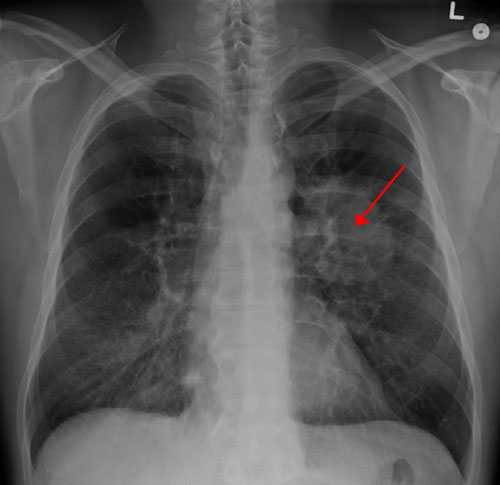

肺癌一滴血早篩?哈佛大學(xué)麻省總醫(yī)院:不久的將來有望實(shí)現(xiàn)

從全球范圍來看,肺癌的“癌王”地位已連續(xù)多年未被撼動(dòng),是癌癥第一大死因。

以往肺癌一直是全球發(fā)病率最高的癌癥,在2020年首次被乳腺癌超越,但肺癌發(fā)病率仍然有220萬/年,位居全球第二大癌癥。

好醫(yī)友腫瘤精準(zhǔn)醫(yī)療專家Michael Castro博士(曾多年獲批“美國頂級(jí)專家”)介紹,肺癌死亡率高,除了其本身的復(fù)雜性外,主要原因在于確診時(shí)常常已是中晚期,而早期肺癌與晚期肺癌的生存率有天壤之別。

早期肺癌大多無明顯癥狀,目前檢測(cè)肺癌篩查的主要手段是低劑量螺旋CT,但考慮到輻射等問題,不少人對(duì)這種篩查手段心存抗拒。

近日,發(fā)表在《美國國家科學(xué)院院刊》上的一項(xiàng)由麻省總醫(yī)院領(lǐng)導(dǎo)的研究顯示,在不遠(yuǎn)的將來,通過一滴血篩查肺癌將成為現(xiàn)實(shí)。

研究人員表示,該研究證明,在不遠(yuǎn)的將來有望開發(fā)一種用于早期檢測(cè)肺癌的敏感篩查工具。他們構(gòu)建的預(yù)測(cè)模型可識(shí)別出肺癌高危人群,然后再將這些可疑病例通過影像學(xué)檢查(如低劑量CT)進(jìn)行進(jìn)一步評(píng)估,以明確診斷。